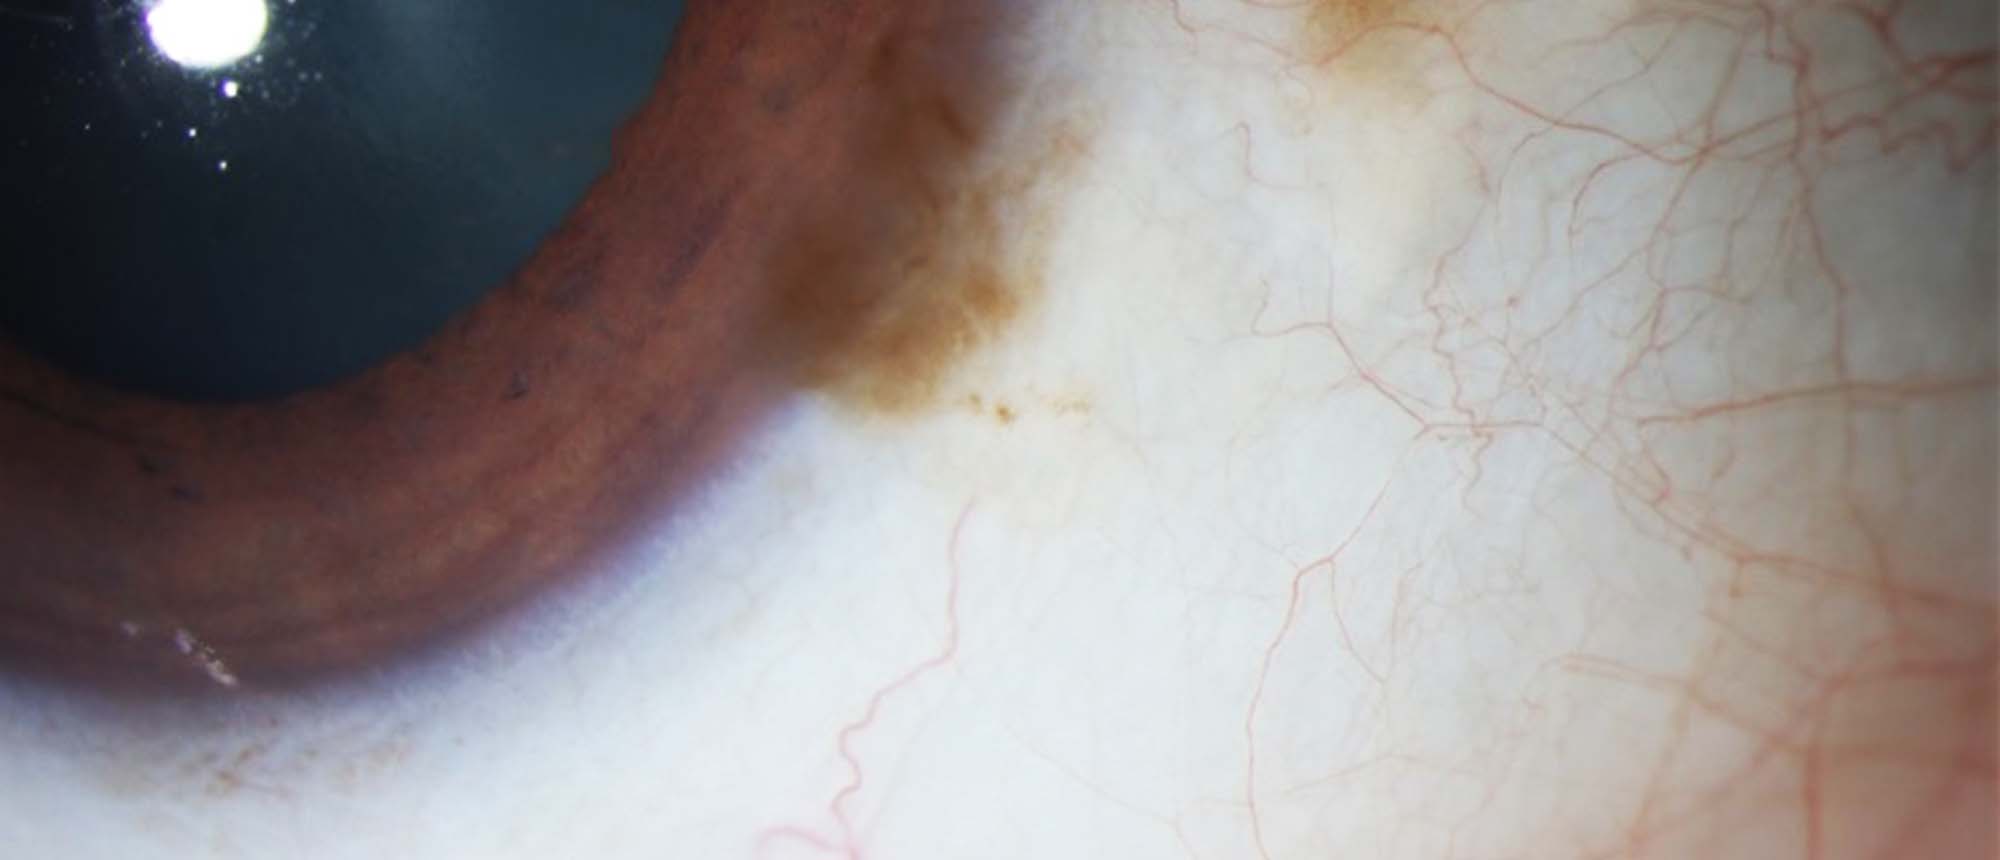

Pseudophakic Bullous Keratopathy with Prior Descemet Membrane Tears due to Forceps Trauma

Presenter(s): Christopher Seery, MD

Faculty Discussant(s): Ellen Koo, MD

Abstract A patient with a history of forceps trauma at birth and amblyopia of the left eye who presents with persistent corneal edema 1 year after uncomplicated cataract surgery. Initial visual acuity was 20/200, intraocular pressure was 10, and pachymetry was 698 um. On clinical examination there …